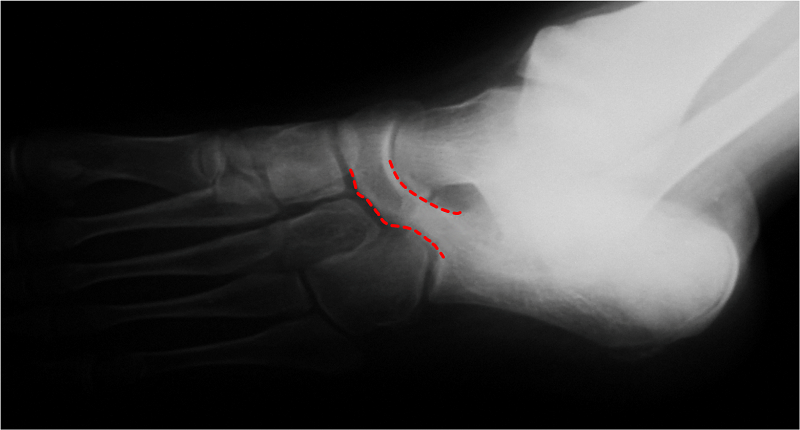

O diagnóstico radiológico é feito através de exames de raio X e tomografia computadorizada.

RX - Coalizão Calcâneonavicular

Na avaliação do exame de raio x, não é raro o médico passar despercebido pelo diagnóstico de coalizão tarsal, pois algumas são difíceis de serem visualizadas, principalmente as coalizões fibrosas e cartilaginosas.